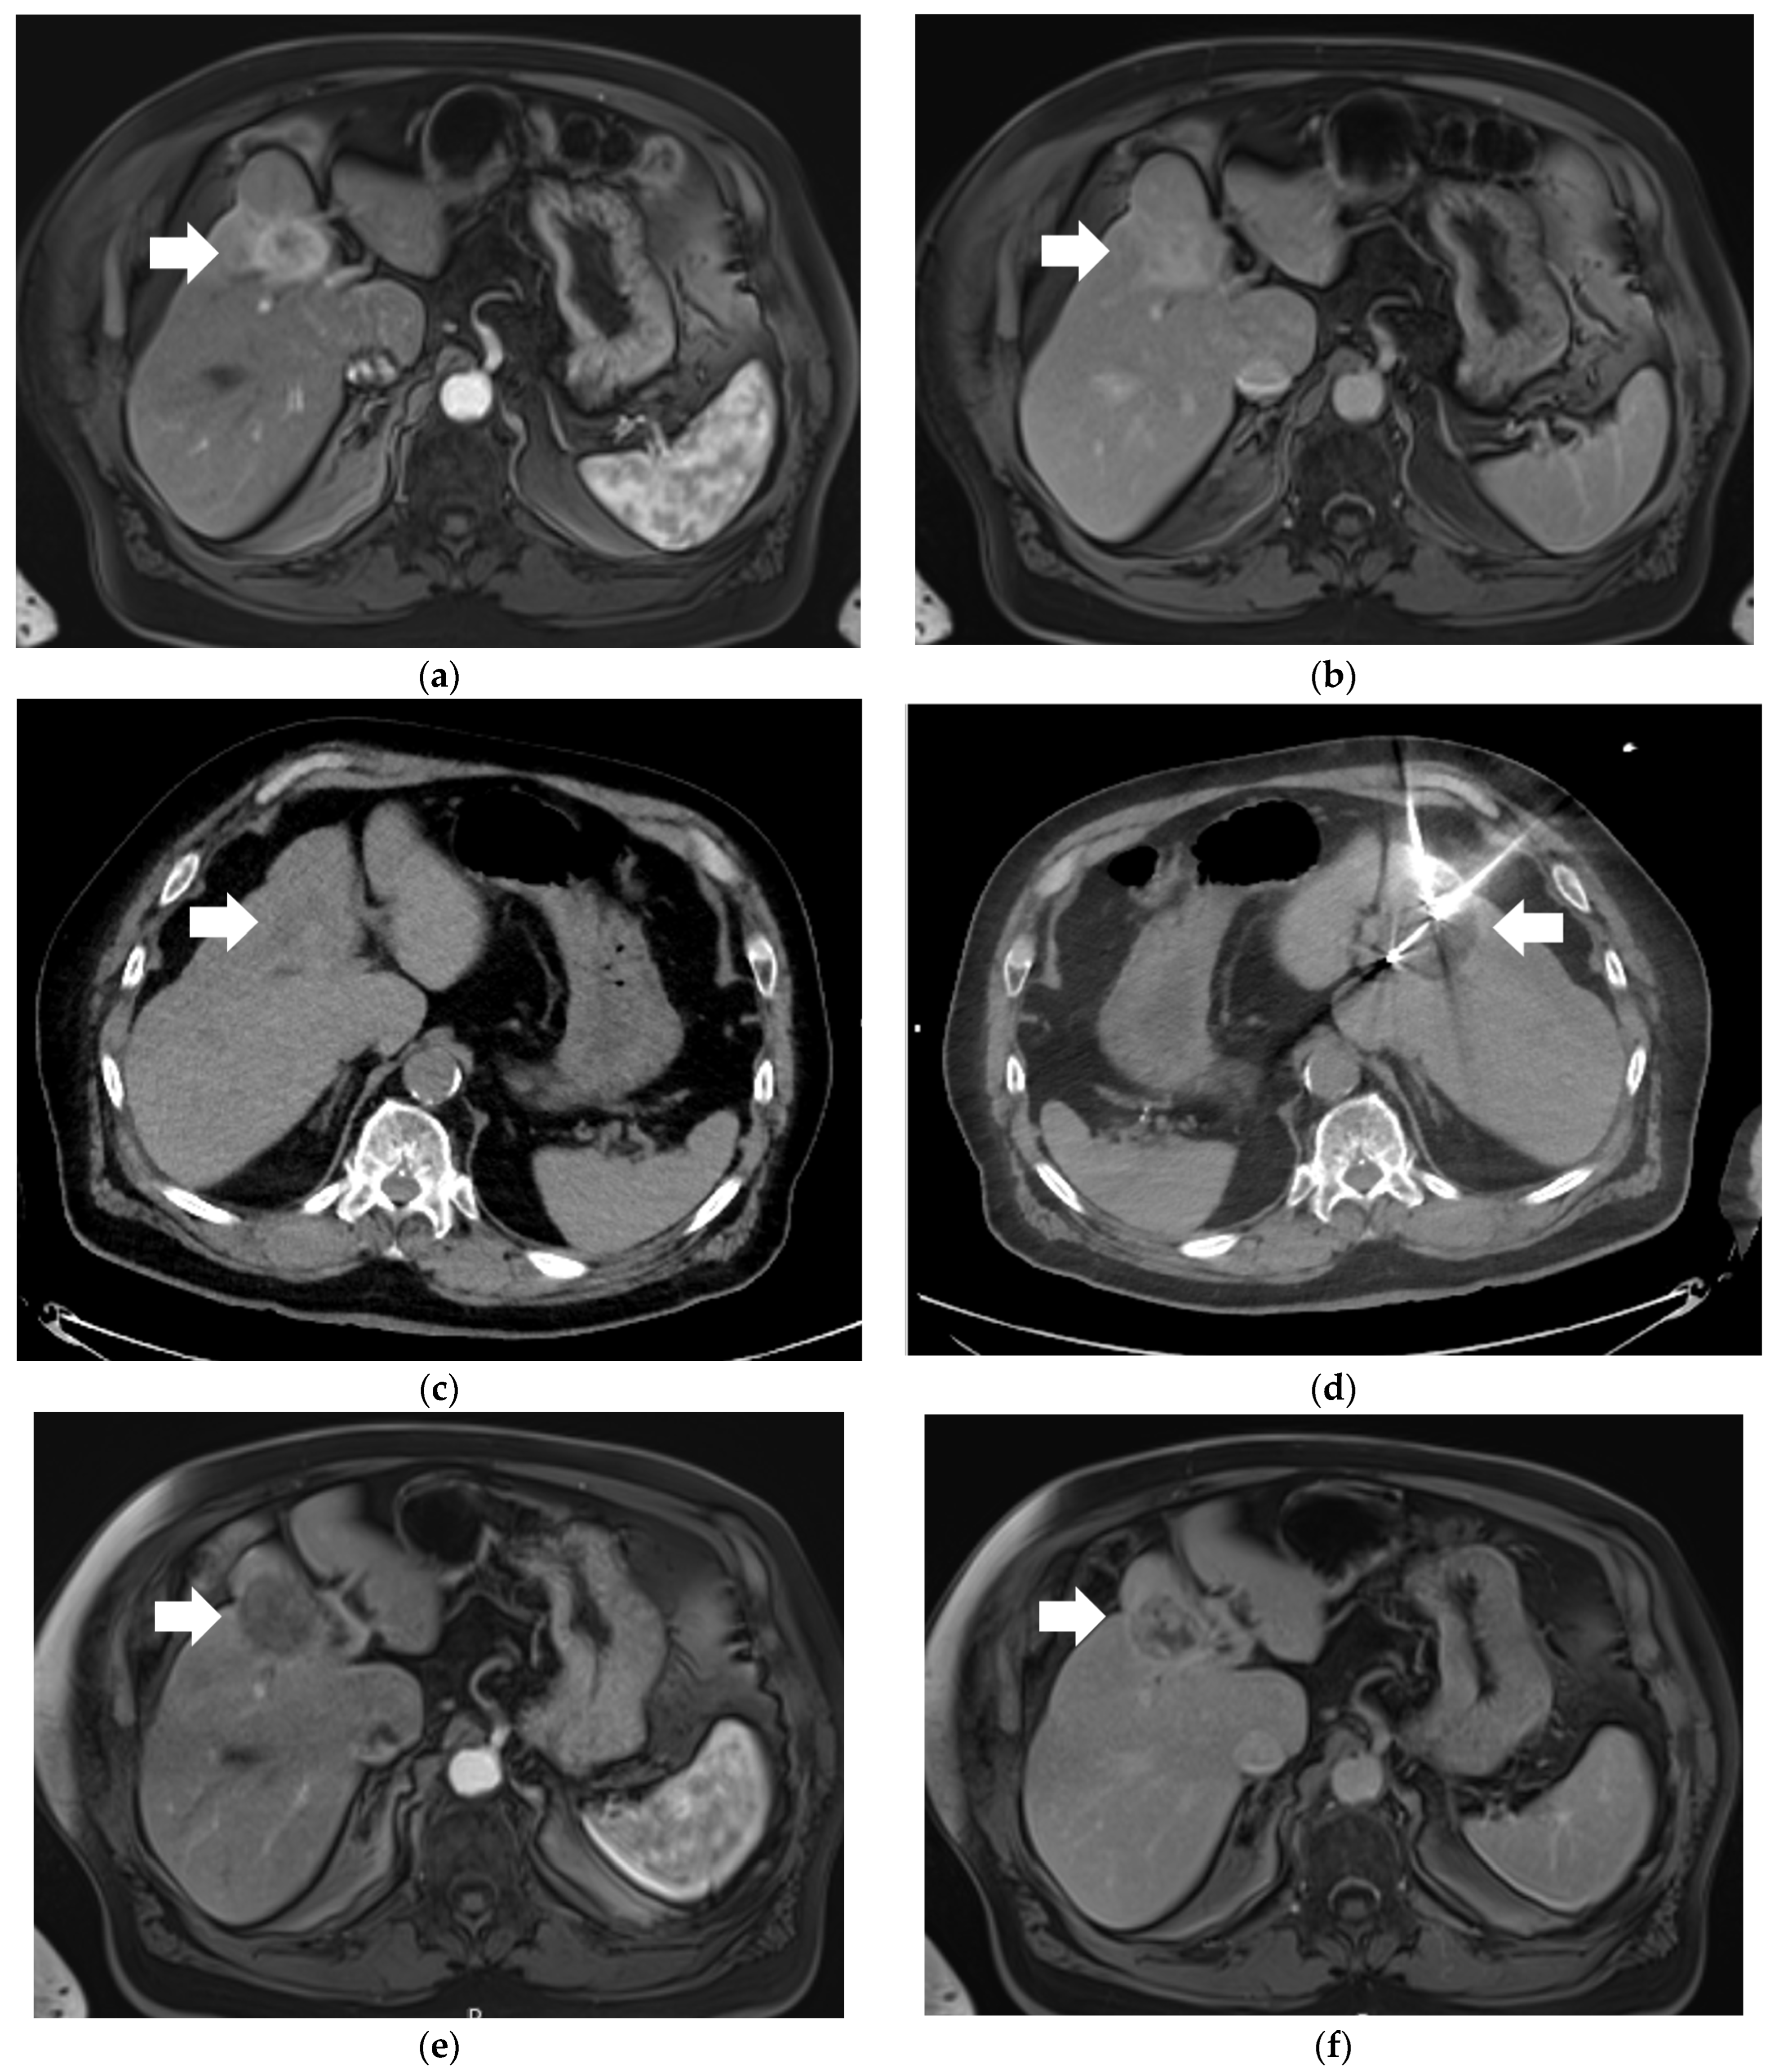

| (a) | (b) | (c) | |

|---|---|---|---|

![]() | ![]() | ![]() | |

| Clinical Scenario | Unresectable iCCA or nonsurgical patient | Locally advanced iCCA | Metastatic iCCA |

| IR Locoregional Treatment | Percutaneous ablation (RFA/MWA, cryo, or IRE) vs super-selective Y90 or TACE | Y90 or TACE | May be appropriate depending on the size/number of iCCA |

| Goal(s) | Local control or curative intent | Local control or downstaging as bridge to surgical resection | Achieve control in the liver |